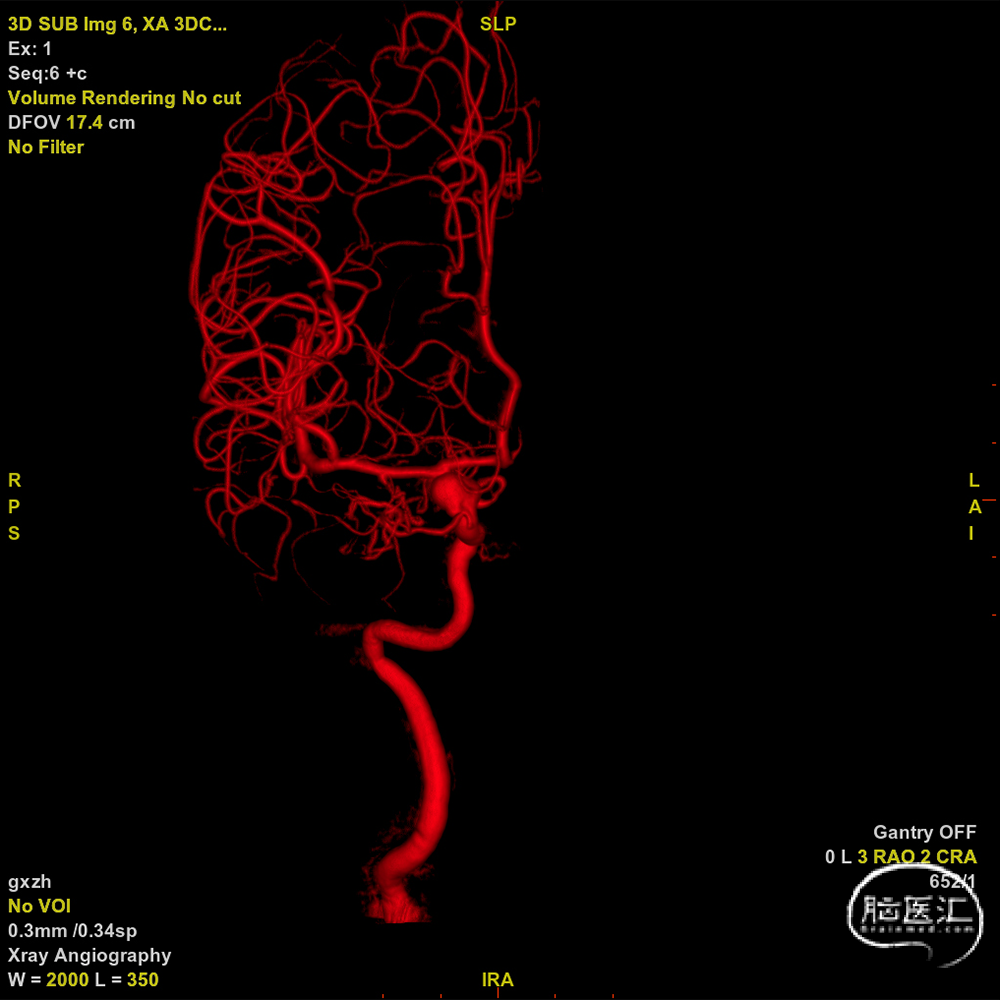

术前影像

DSA右侧颈内

DSA左侧颈内

3D-DSA重建结果。